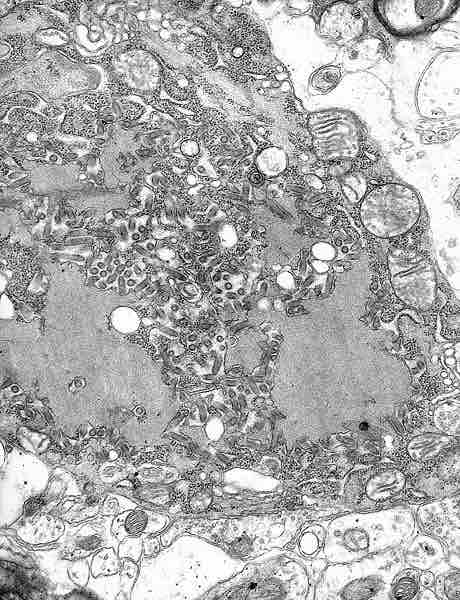

Electron Micrograph of the Rabies Virus.

This electron micrograph shows the rabies virus, as well as Negri bodies, or cellular inclusions.